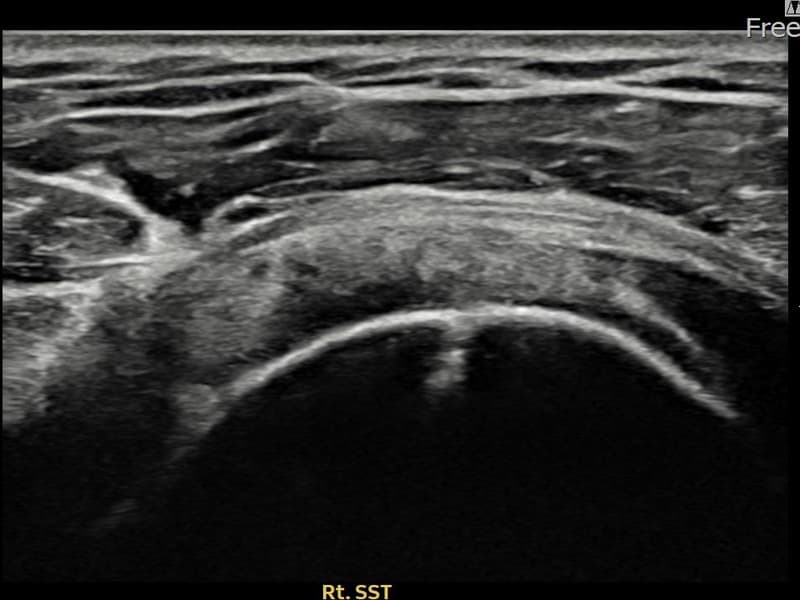

施術後

術前超音波にて右 棘上筋腱 関節面側部分断裂・右肩棘上筋腱のエコー不連続と腱欠損(9mm × 4mm (腱厚の約38%欠損))を確認。術後超音波では断裂部位が再生組織で充填され、腱の連続性回復とエコーパターンの正常化が確認されました。